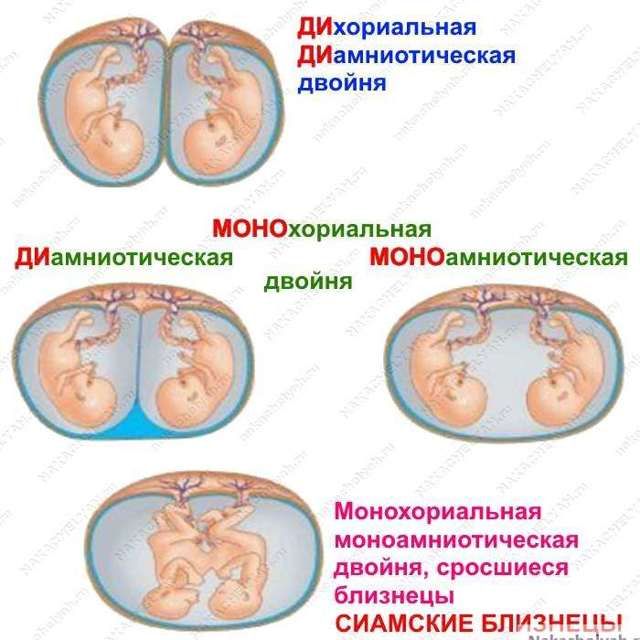

Перегородку, пока, не видно, поэтому монохориальная моноамниотическая двойня. Чуть позже могут увидеть перегородку и будет монохориальная диамниотическая

Таро Расклады, нет первый вариант это Ди-Ди с этой двойней два плодных яйца и каждый в своем домике,а у автора одно пя на двоих это моно-ди

Таро Расклады, и что ?:) прикрепились и прикрепились ) пуповинки же разные...

ди ди на Узи сложно спутать ) там прям два отдельных домика, например:

Пока что это монохориальная моноамниотическая, позже могут найти перегородку

Хорион один, плодный пузырь один==> монохориальная точно, но вот диамниотическая или моноамниотическая скажут позже, все зависит от того найдут ли между ними внутри плодного пузыря перегородку, чаще их находят, ну это и лучший вариант чем моно моно. Вообще, такие двойни спокойно могут быть ди ди, ди ди это не только когда два разных плодных яйца, это когда у каждого свой амнион и своя плацента именно тогда двойня будет ди ди.

Монохориальная диамниотическая,одно плодное яйцо это Моно,а остальное по два,это Ди

МоноДи скорее всего. Близнецы, а не двойняшки. Будут одного пола. Поздравляю Вас🌷🌷🌷. Чихните заразным чихом😉